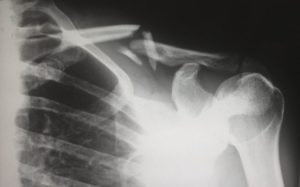

Røntgenundersøgelse

04 March 2023